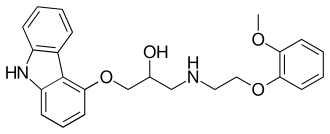

| Carvedilol | Coreg

Coreg CR |

|

Blocks some α1 receptor activity, but binds more strongly to β receptors.[2] | Can interfere with noradrenergic mechanisms.[2] |

|